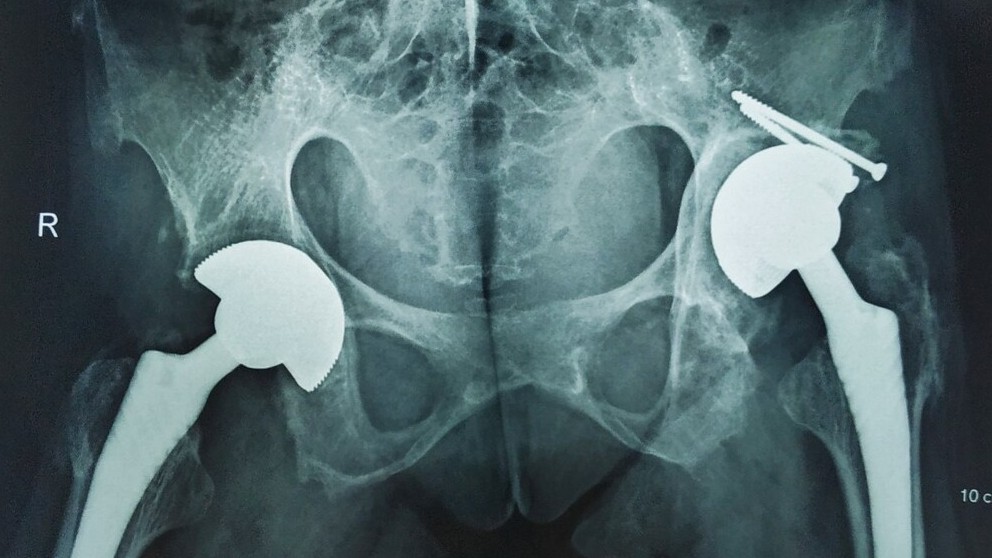

Đi lại được sau 30 năm nằm bệt

Thời sự xã hội -  08/04/2021

Trước đó, mọi sinh hoạt của chị phụ thuộc vào người thân. Khi thăm khám tại Bệnh viện Hữu nghị Việt Đức, chị được các bác sĩ chỉ định phẫu thuật bởi c...